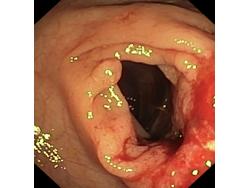

Krwawienie

Nowotwory przewodu pokarmowego

Zabiegi endoskopowe